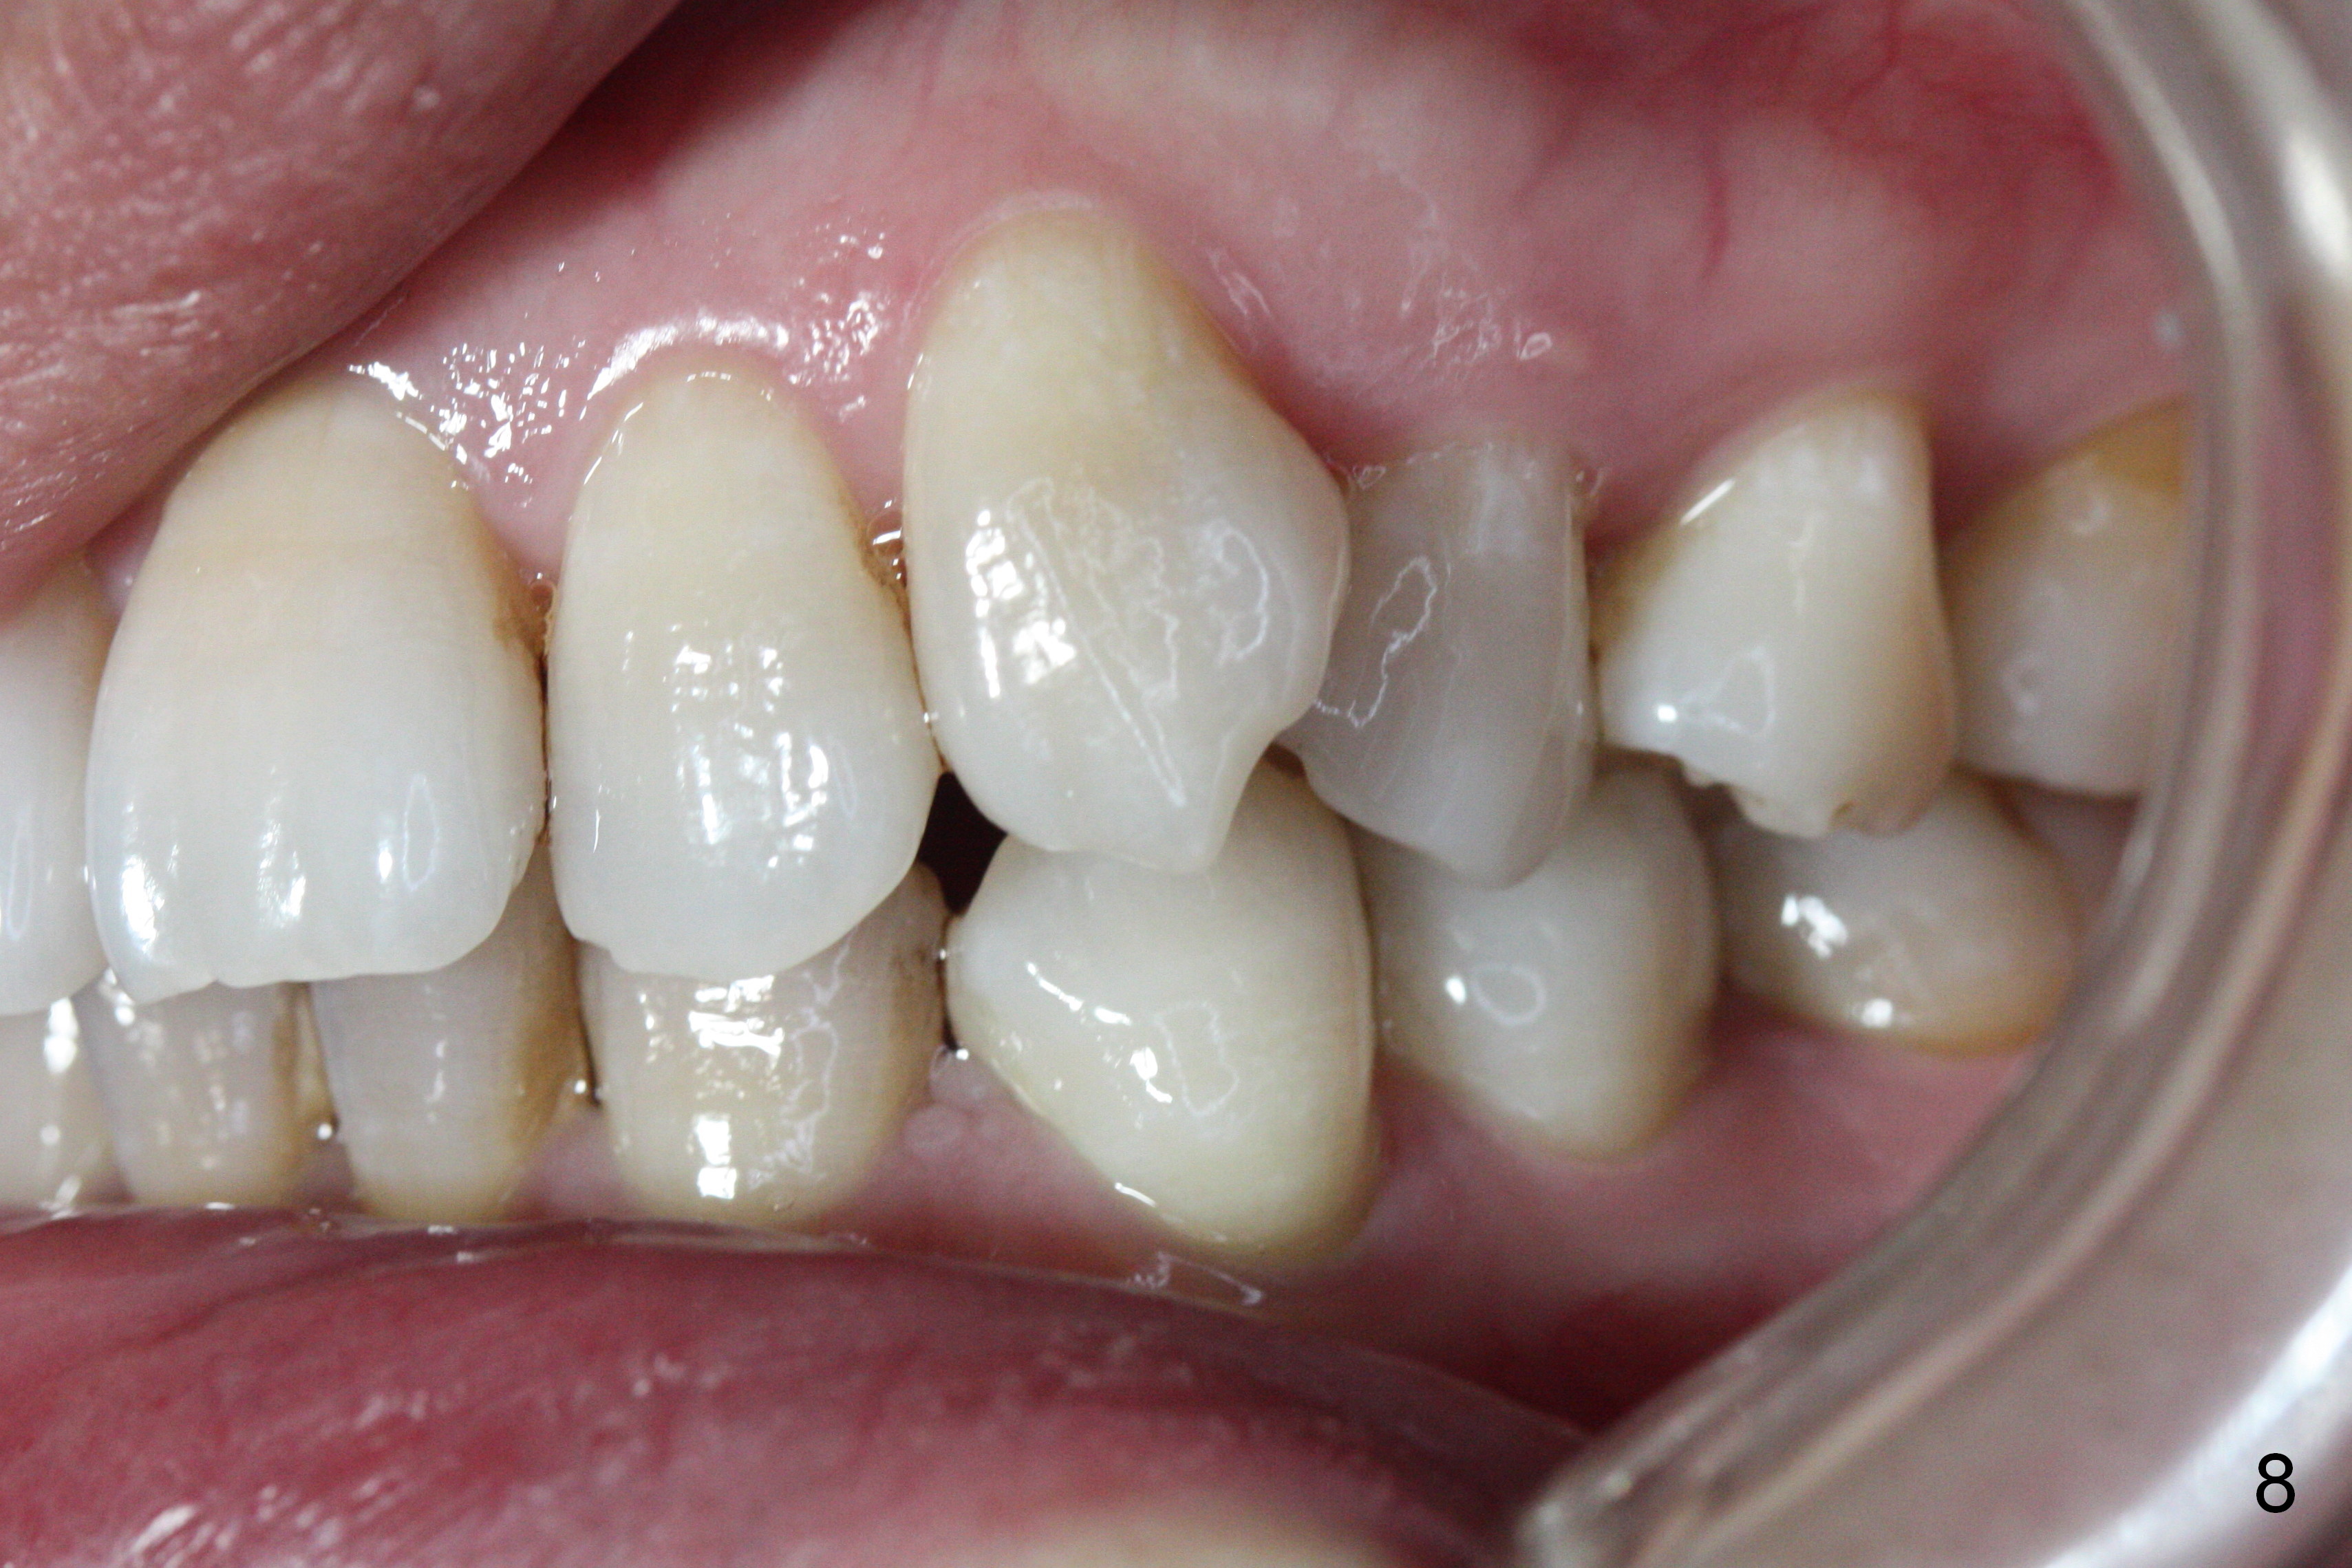

A 41-year-old woman requests orthodontic treatment because of the upper blocked out canines (Fig.6,8). Her facial and dental midlines coincide (Fig.1). Her profile is slightly convex (Fig.2,3) with increase in overjet (Fig.4). Orthodontic treatment includes extraction of U4s and placement of 2 mini-implants between U5 and 6 (Fig.5 o) when arch wires change to 18x25. Power arms (as high as possible) are placed between U2 and 3. U1-3s are retracted at the same time (en mass) because of absolute anchorage of the mini-implants. Retraction time will be reduced. Interproximal reduction (IPR) will be done especially at LR3 (macrodontia, Fig.5) if the lower arch turns out to be too large.